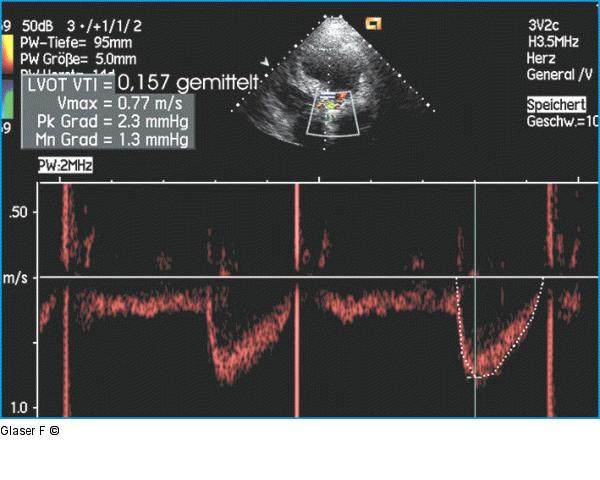

Abbildung 6: Gepulster Doppler - LVOT Gepulster Doppler des linksventrikulären Ausflußtraktes (LVOT): niedrige Geschwindigkeit, niedriges Velocity-Time-Integral (VTI). Das Verhältnis LVOT/VTI/Aortenprotesen-VTI von nur 0,23 ist niedrig (normal bei Zweiflügelklappenprothesen 0,41 ± 12), woraus sich bei einem LVOT-Durchmesser von 20 mm eine errechnete Prothesenöffnungsfläche von 0,73 cm2 ergibt. |